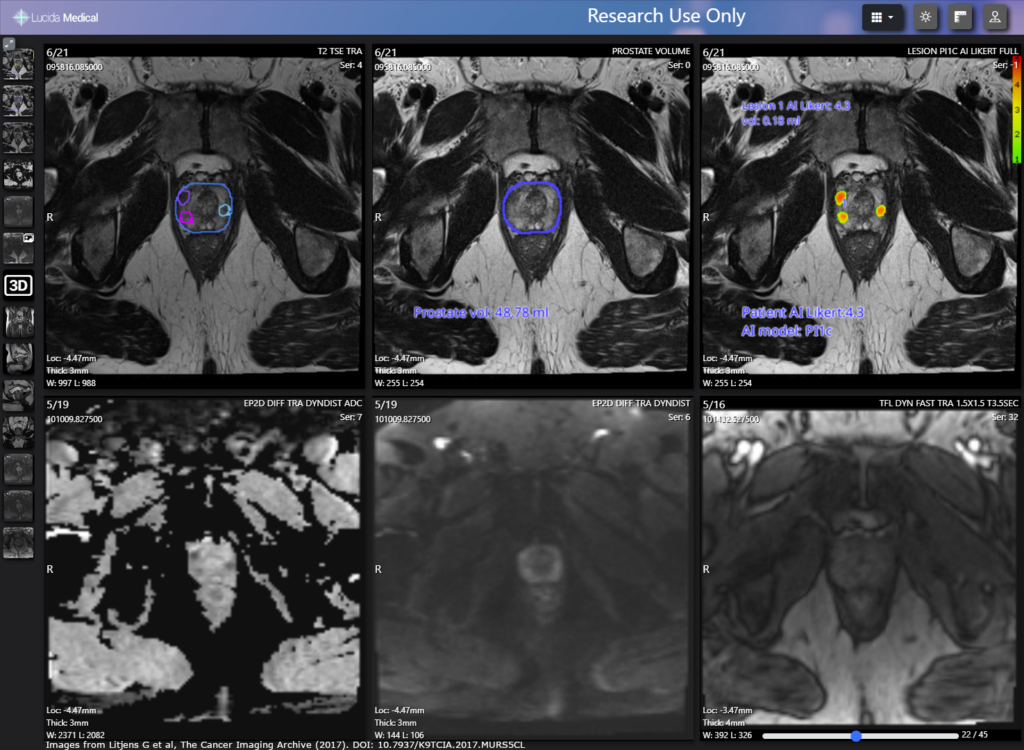

Pi™, Prostate Intelligence, is a CE-marked AI software system that supports the prostate MRI reading workflow of radiologists. Developed by Lucida Medical, Pi™ uses machine learning to improve patient selection for biopsy, identify regions of interest and generate high quality segmentations.

The software first helps radiologists prioritize patients using risk scores. Low risk patients may forgo biopsy for now, reducing the risk of overtreatment and allowing high risk patients to be seen sooner. After the MRI, Pi™ characterizes lesions by location and size. Its high negative predictive value ensures all regions of interest are targeted for biopsy, reducing the risk of underdiagnosis. In the final step of MRI interpretation, Pi™ automatically segments the prostate. Compared to human expert annotations, the software has a high DICE score, meaning the contours are on par with experienced radiologists.